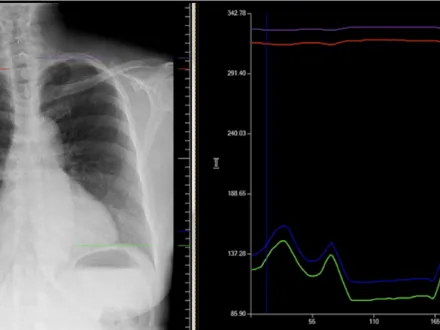

DDR is a non-invasive cineradiography imaging technique that acquires up to 15 sequential radiographs per second and processes them as a cine loop, enabling clinicians to observe the physiological cycle as well as individual radiographs. This novel, low-dose advancement in digital X-ray enables visualization of anatomy in motion with a simple acquisition.

The seven RSNA 2025 presentations further demonstrate the clinical value of DDR in radiography across a broad range of clinical conditions: interstitial lung disease, COPD with emphysema, lung cancer, pulmonary thrombo-embolism (PTE), perfusion abnormalities, ventilation function and pulmonary blood flow assessment. Collectively, these studies report that DDR provides a contrast-free, non-invasive method for imaging lung diseases, lesions and emboli, investigating functional pulmonary impairment and assessing ventilation in diseased lungs. Additionally, the chest studies described in the research below do not use contrast, which is unique for cardiac imaging and pulmonary perfusion exams. And, as noted by Cellina et al., portable DDR delivers new opportunities for identifying ventilation disparities and evaluating respiratory interventions in Intensive Care Units.

Dynamic Digital Radiography-Derived Perfusion Indices Reflect Structural and Functional Impairment in COPD with Emphysema: Okada et al. compares DDR with spirometry and high-resolution CT as a possible quantitative biomarker for pulmonary emphysema in patients with chronic obstructive pulmonary disease (COPD). The authors report that the diagnostic performance of DDR correlates with CT and Goddard Scores, demonstrating good diagnostic performance. As important, DDR provides pulmonary perfusion mapping and quantifies functional impairment, a capability that remains limited with CT and spirometry. Masahiro Okada, MD, PhD, Nihon University Itabashi Hospital, Tokyo, Japan, will present the findings in Session R4-STCE2, December 4 in the Learning Center Theater 2.